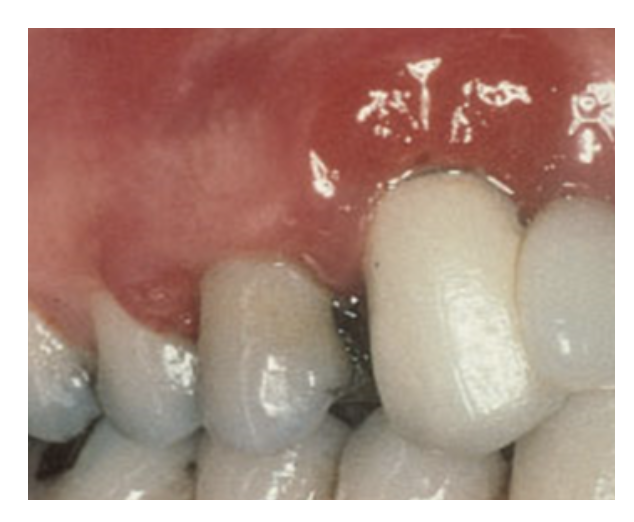

For cementing in self-cure mode, look for a cement that can be cured in any modality and that does not require an additional catalyst with the preferred bonding system. The chemical curing reaction is extremely important when cementing a substrate in a situation where the curing light cannot reach or the light cannot penetrate the substrate.25This also is important because film thickness may be a concern-some bonding agents' film thicknesses may be higher than others and it is best to avoid adding another activator. Increased material film thickness and viscosity, whether on the substrate surface or on the tooth surface, may prohibit a restoration from being seated fully and result in failure to achieve a marginal seal. It may also result in requiring increased force to seat the restoration, which may in turn cause thin and fragile ceramics to become damaged or fracture. Cements from some manufacturers use a universal catalyst because their dentin bonding agents inhibit the curing of the self-cure portion of a dual-cure resin cement.26 Proper handling of the cement is crucial. Residual cement can cause crown failure, soft tissue inflammation, gum recession, peri-implant inflammation, and peri-implantitis (Figure 6).27-30

In the next case, the practitioner used a zirconia crown to replace an e.max crown on tooth No. 23 that had brown staining/discoloration. The practitioner used a universal to place the zirconia crown.  Excellent gum tissue health also was a result.

The next case was particularly challenging as the patient was congenitally missing tooth No. 10 and had an undersized lateral tooth No. 7. A different practitioner had placed an implant too high, presenting challenges with the gum. The patient declined tissue conditioning or training, adding to the difficulty of the case. The practitioner cemented a veneer and did a custom abutment, using a universal cement to bond to the enamel of No. 7 and to the titanium at No. 10. Cement offered easy cleanup and was radiopaque, allowing the practitioner to make sure no cement was left behind, which could cause peri-implantitis.

In another case, the patient presented with very thick, bulky, over-contoured veneers done on teeth Nos. 7 through 10 when she was a teenager. There also was some recession and staining at the margins (Figure 12). The clinician decided to restore teeth Nos. 6 through 11. A preparation design was required with provisionals removed. As tooth structure could not be regrown, the practitioner made the best of the situation. There was good gum health, which is important for isolation and marginal seal. The clinician cemented with a universal, doing six units at one time. Minimal cleanup was required. At a 1-month follow-up visit, although tissue still was settling in, the contours were natural. After a year (Figure 13), the gum filled in nicely and was in excellent health, and there was good color stability and seamless marginal integrity.